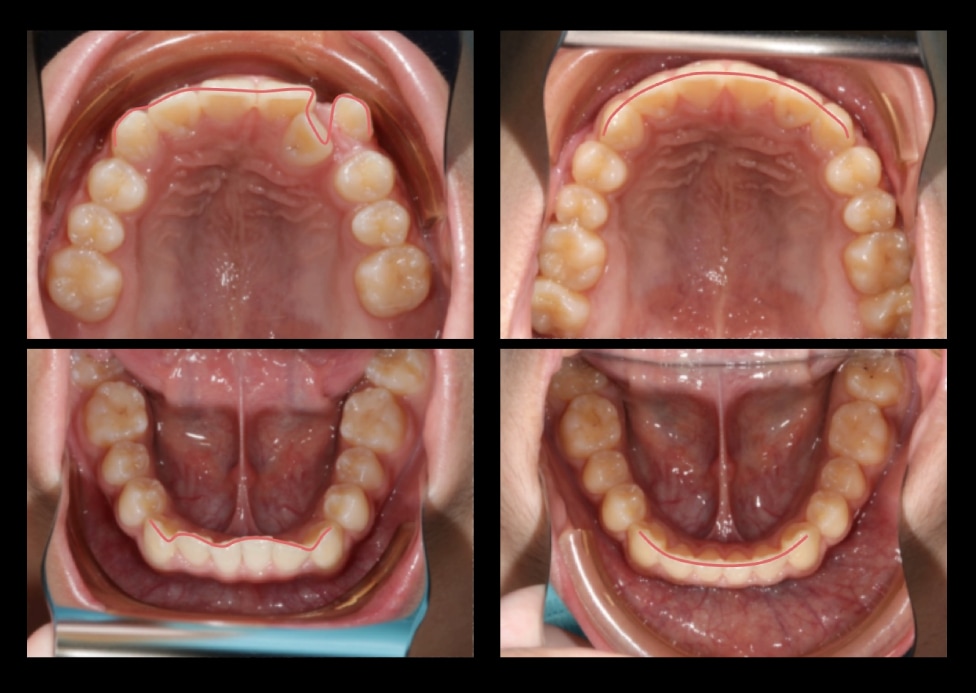

Case 3. 牙齒擁擠(不拔牙矯正)

• 主訴:改善牙齒擁擠但不拔牙

• 治療方式:由於患者為男性且鼻子挺、又有下巴,沒有美觀線(輪廓線)內收的需求,因此利用上排後牙依序往後退(sequential distalization)及較大量的擴弓(expansion)來創造出左上側門牙及高犬齒的排齊空間。